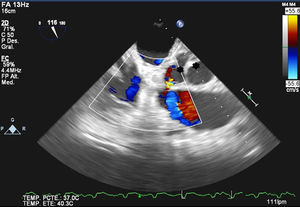

Sixty-six year-old patient with a mechanical aortic prosthesis implanted two months ago, who recently experienced a deterioration in his level of consciousness and a sudden-onset fever of up to 39°C, along with a bluish nodular lesion in the fifth digit (little finger) of his left hand. The brain CAT scan performed revealed a parietal intraparenchymal hemorrhage, of which blood cultures were taken (with a positive result for Staphylococcus aureus). Furthermore, the transthoracic echocardiogram (TTE) carried out showed a poorly differentiated hyperechogenic image at the level of the prosthetic valve. Based on the above findings, a transesophageal echocardiography (TEE) was also performed revealing the presence of a metallic aortic valve prosthesis associated with periaortic thickening (arrow, Fig. 1) along with images of cavitated lesions in the posterior end of the aortic root (asterisk, Fig. 2), one of which was seen to come into contact with it, thus being suggestive of a complicated endocarditis. Additionally, a cardiac CAT scan showed a 9-mm heart wall defect coming into contact with a 9×6×5.5-cm collection, as well as contrast media extravasation suggestive of a broken pseudoaneurysm contained by the epicardium (arrow, Fig. 3). This case report brings to light the key role of TEE in detecting cases of endocarditis.